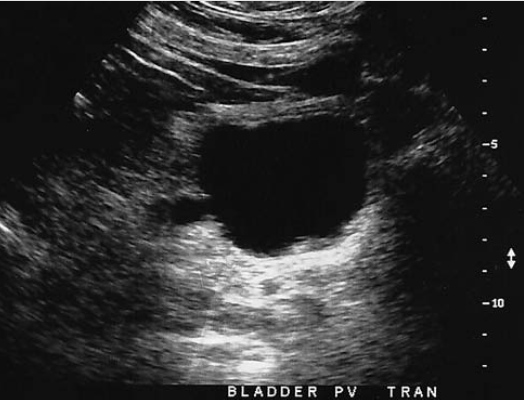

when hydronephrosis is encountered, the sonographer should evaluate urinary bladder for

obstruction